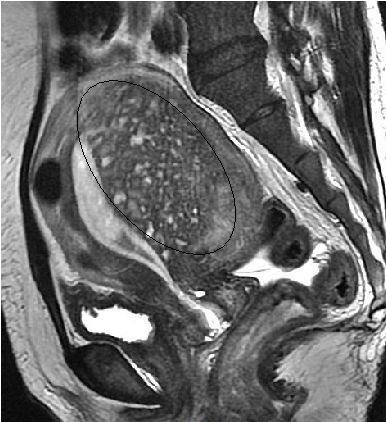

A ressonância magnética (RM) é hoje considerada um dos melhores métodos para o diagnóstico preciso da adenomiose. Ela permite uma visualização detalhada das camadas do útero, identificando alterações na espessura da zona juncional e características como lesões císticas, focos ectópicos e alterações difusas no miométrio.

💡 Principais achados na imagem por RM

- Espessamento da zona juncional (acima de 12 mm)

- Presença de pequenos focos hiperintensos em T2

- Aspecto "borrado" entre endométrio e miométrio

- Lesões císticas intramiometriais